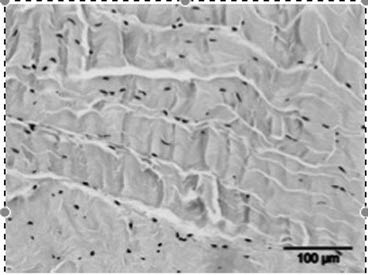

- Het stimuleren van de collageenproductie en het afvoeren van beschadigd collageen, wat resulteert in een verhoogde matrix-turnover.